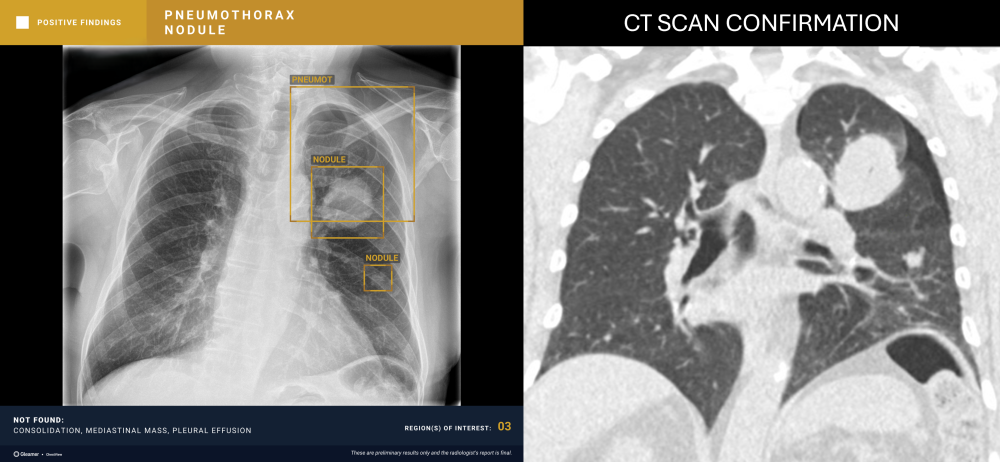

Indication

A 40-year-old female with a history of colon cancer presents for a control radiograph following biopsy of a right lower-lobe pulmonary nodule.

Results

ChestView detected a pneumothorax post-biopsy.